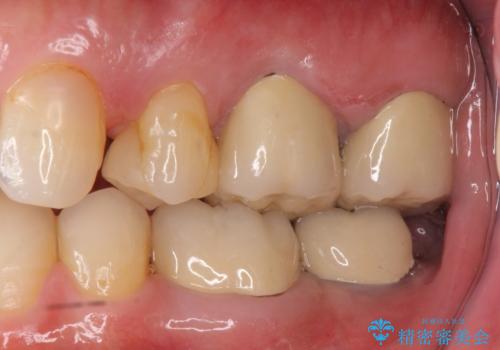

- 矯正治療・銀歯のやりかえ希望で来院されました。

矯正治療により歯並びの改善を行いつつ失われた最後方臼歯をインプラントを用いて咬合機能回復します。

- 40万円(ストローマンインプラント・カスタムチタンアバットメント・メタルボンドクラウン)費用は治療当時の料金となります

最後方臼歯の治療について

最後方臼歯を喪失した場合、入れ歯・インプラントによる咬合機能回復方法があります。

今回はしっかりと噛むことができ、取り外しの必要のないインプラントによる補綴を行いました。